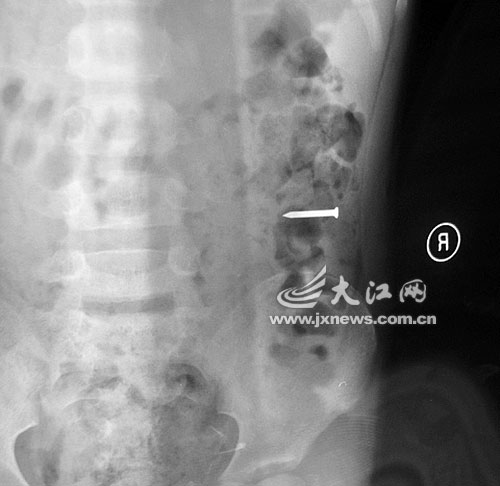

當晚7時20分許,勇勇突然將這枚長達2.5厘米的鐵釘吞進肚子,并疼得渾身冒汗。

事發當晚,勇勇的奶奶雇了一輛面包車,連夜將勇勇送往都昌縣人民醫院救治。當晚,醫院經過拍片發現,2.5厘米的鐵釘滑到孩子的胃部。